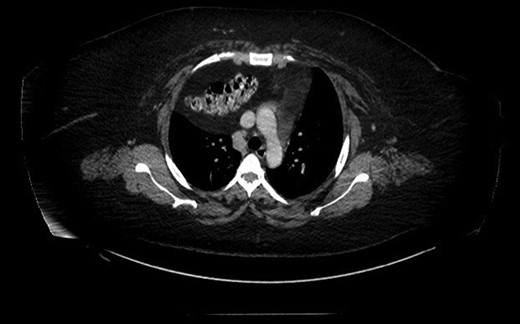

Prior to the surgery patient had symptoms of mild dyspnea, vague abdominal discomfort and an initial evaluation with Chest X Ray revealed bowel gas pattern in the right hemithorax (Fig. 1). A subsequent CAT scan thorax and abdomen revealed a right-sided large morgagni diaphragmatic hernia containing omentum and portion of the transverse colon (Fig. 2). Patient elected to undergo Laparoscopic sleeve gastrectomy and concomitant morgagni diaphragmatic hernia repair. Abdomen was explored laparoscopically which revealed a right sided morgagni diaphragmatic hernia with defect size about 8 × 4 cm, containing omentum, transverse colon and part of the falciform ligament. Contents were reduced successfully taking care not to injure the bowel, falciform ligament partially dissected. A sleeve gastrectomy done. Then the hernial defect was closed primarily by interrupted non absorbable sutures. The closure was then reinforced with a sublay ventralight mesh which was secured using transfascial fixation sutures and with tackers (Fig. 3). The post operative course was unremarkable and the patient was discharged on post operative Day 2 with normal chest X-ray (Fig. 4). At 2 months after surgery the patient was doing well and tolerating solid and liquid diet and no more dyspnea nor GI symptoms.

CAT scan thorax and abdomen revealed a right-sided large morgagni diaphragmatic hernia.